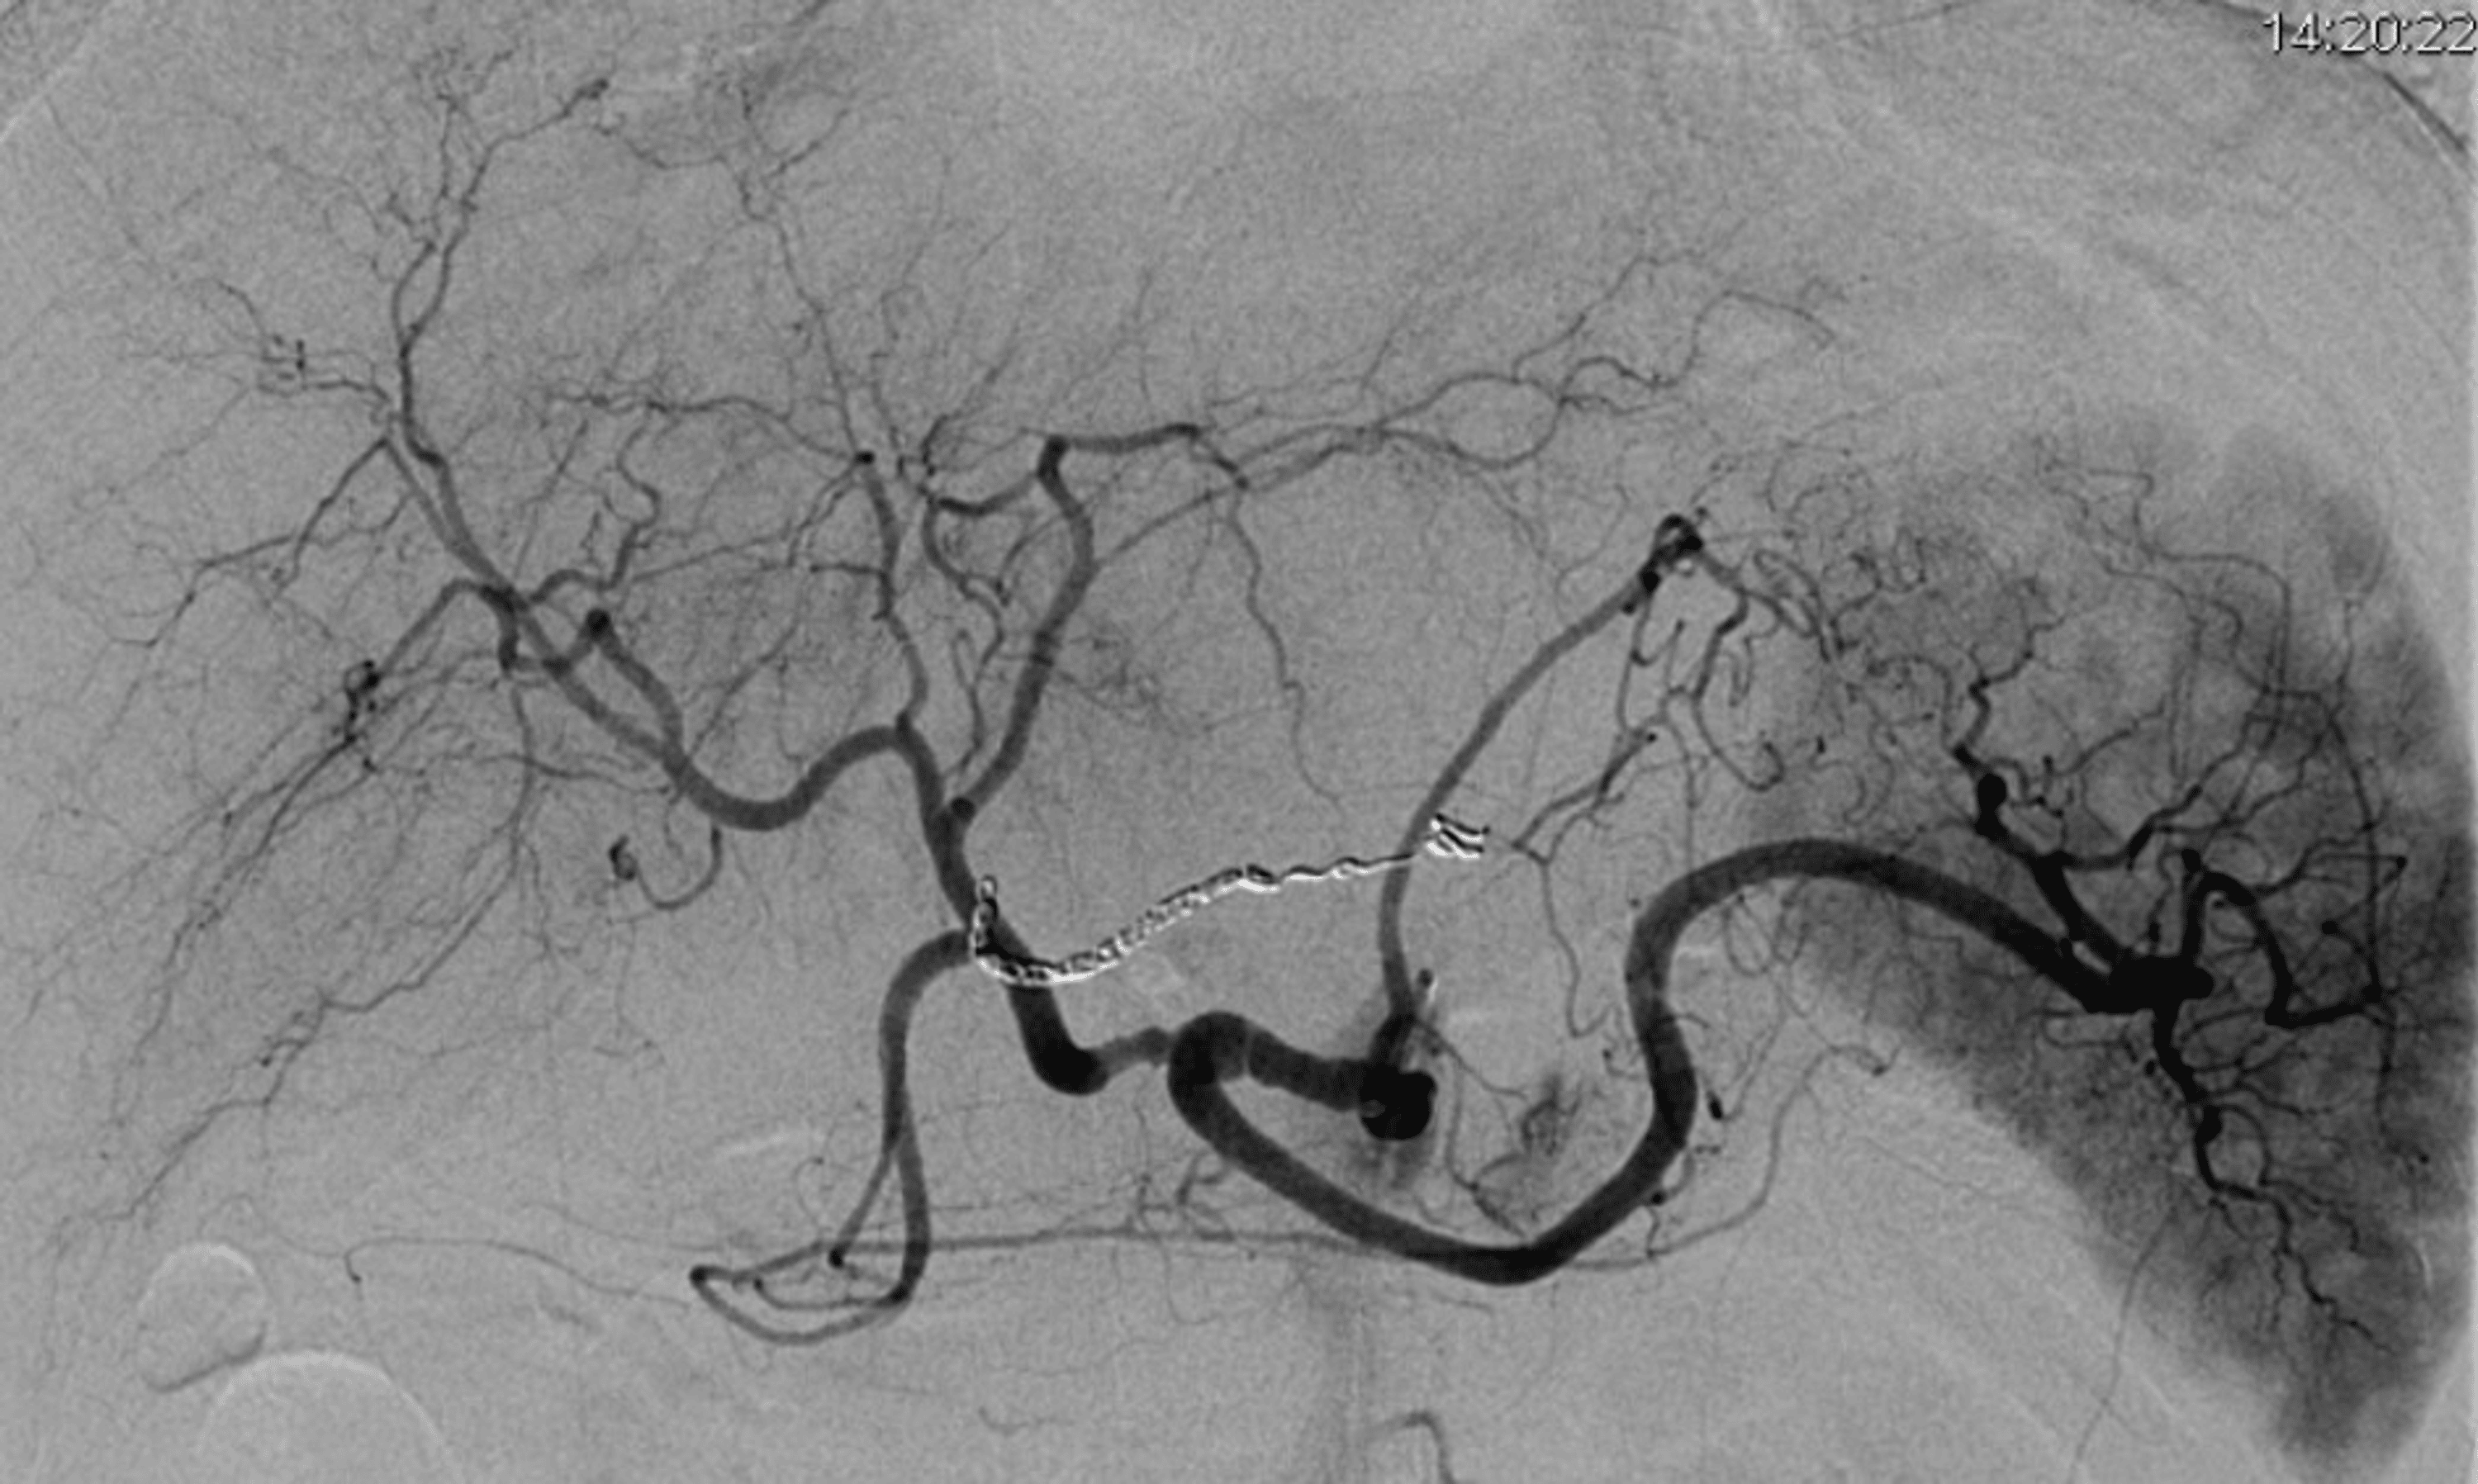

From radiologykey.com

5 Embolization for an Upper Gastrointestinal Hemorrhage Radiology Key Coil Embolization Of Gastric Artery Gastric variceal injection therapy under eus guidance confers potential advantages over conventional endoscopic visualization. Tae is an effective procedure in the treatment of ugib patients in which angiography does not demonstrate direct sign of ongoing bleeding. Eus enhances the precision of. The gastroduodenal artery (gda) is frequently embolized in cases of upper gi bleed that has failed endoscopic therapy. Arteries. Coil Embolization Of Gastric Artery.

5 Embolization for an Upper Gastrointestinal Hemorrhage Radiology Key Coil Embolization Of Gastric Artery Tae is an effective procedure in the treatment of ugib patients in which angiography does not demonstrate direct sign of ongoing bleeding. Arteries primarily embolized were the gastroduodenal artery (n = 30), the left gastric artery (n = 18), the inferior pancreaticoduodenal. Eus enhances the precision of. According to all available published evidence, empiric embolization assessed with endoscopic or preprocedural. Coil Embolization Of Gastric Artery.